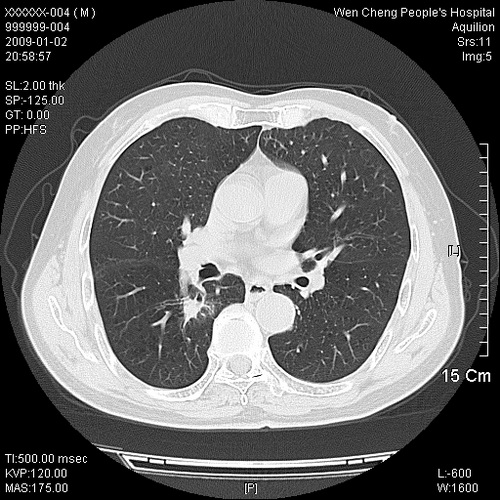

男性,73岁,有慢支病史,肿瘤系列标志物检验正常,血沉及血常规正常

右肺下叶背段小片状 磨玻璃样模糊影,内见血管及含气支气管像,支气管管壁增厚。考虑:慢性炎症!

右肺下叶背段小片状 实性与磨玻璃样影,内见血管及含气支气管像,支气管管壁增厚,边缘见长毛刺影。考虑:慢性炎症或肿瘤!建议抗炎治疗复查,密切观察随访!

右肺下叶片团状影内见扩张的含气支气管和支气管管壁增厚,其周有磨玻璃样模糊影和长毛刺。考虑慢性炎症可能性大。

2、右肺下叶片团状影内见扩张的含气支气管和支气管管壁增厚,其周有磨玻璃样模糊影和长毛刺。考虑周围型肺ca可能,结核不排。

高度提示细支气管肺泡癌,建议抗炎治疗半月观察病灶变化,如无明显改变,建议立即手术治疗.

病变形态非常不好呀,临床上血常规及症状也不明显,不太支持炎性病灶,高度警惕肿瘤病变,最好做个纤支镜检查。